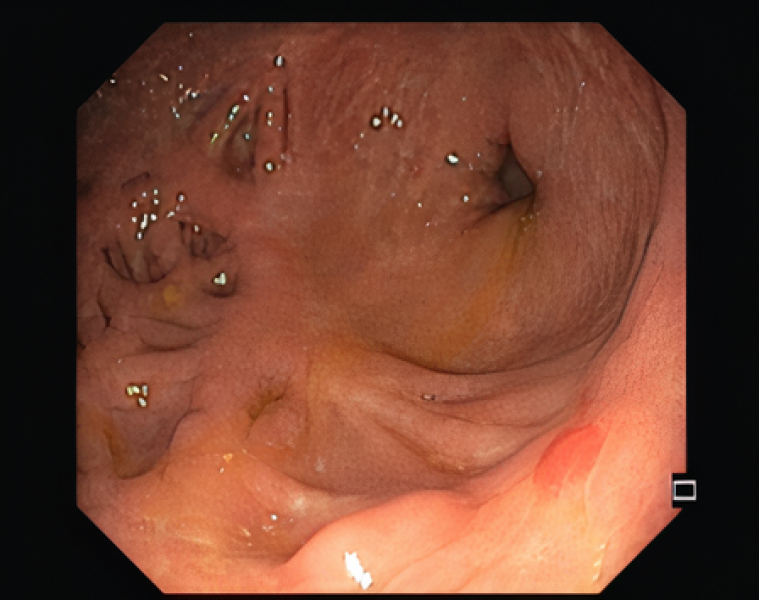

An uncommon cause of bowel obstruction in Ulcerative Colitis